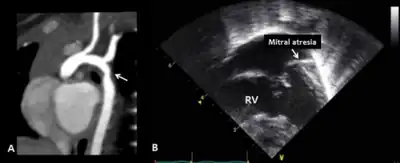

| Symptoms | Vary widely among patients but may include: Long eyelashes, depressed nasal tip, atypical fingerprints, ear deformity (macrotia or microtia), hypotonia, joint hyperflexibility, ptosis, blue sclera, cafe au lait spot, GU anomalies (e.g. hypospadias or horseshoe kidney), gi anomalies (e.g. anal atresia or intestinal malformation), hearing loss, immune deficiencies (e.g. hypogammaglobinemia), feeding difficulty (infants), obesity (adulthood), short stature, poor sleep, hyperinsulinemia (hypoglycemia), epilepsy, cardiac defects (e.g. coarctation of the aorta), vertebral anamolies (e.g. butterfly vertebrae), sparse lateral eyelash, finger anomaly (e.g. short 5th finger), cleft palate, dental issues, precocious puberty, scoliosis, hip dysplasia |